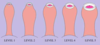

What is phimosis?

- Foreskin cannot be fully retracted from around the tip of the penis

- Normal to be non-retractable in adolescence, e.g 50% cannot be retracted at 1 year

What is paraphimosis and what are the most commonest causes?

- Foreskin can no longer be pulled forward over the tip of the penis causing the foreskin to become swollen and stuck

- Phimosis, Catheterisation (esp the elderly) and Penile Cancer are all causes

How do you treat phimosis and paraphimosis?

- Circumsion for phimosis (be careful if have phimosis and balantis, may have underlying cancer)

- Needs reduction manually or dorsal slit may be necessary